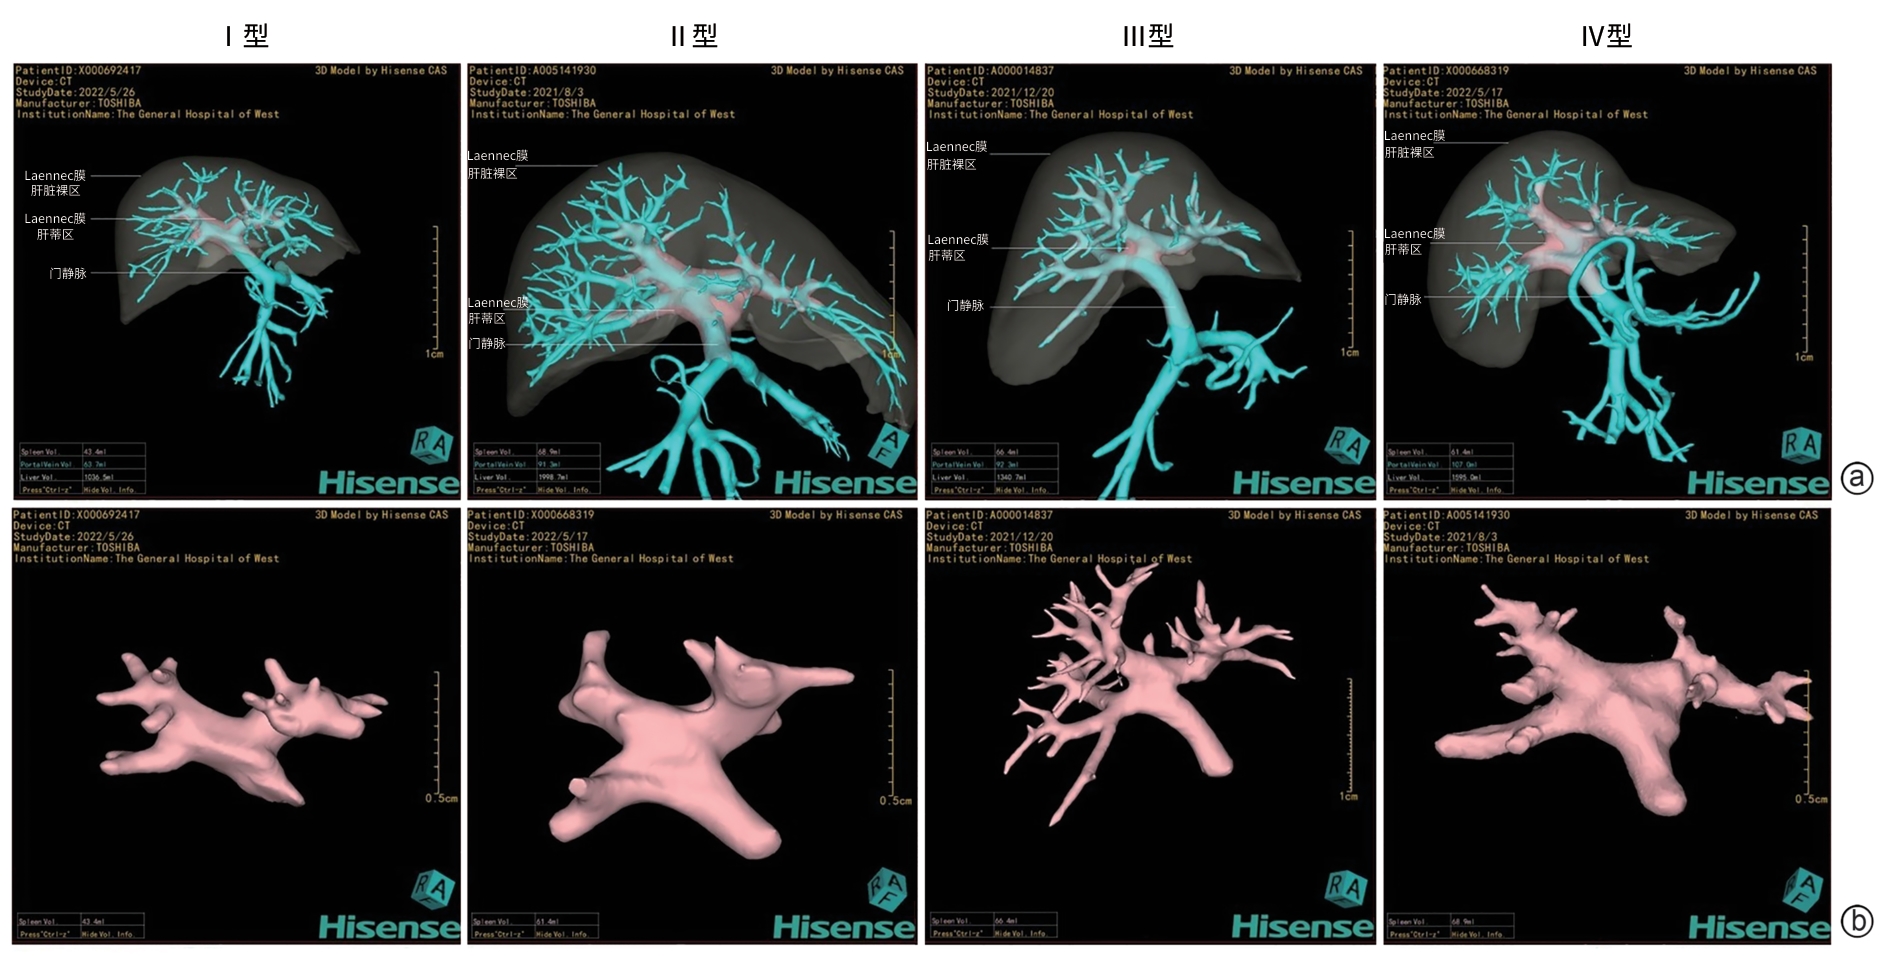

Three-dimensional CT reconstruction of the hepatic pedicle based on the Laennec’s capsule and the development and validation of extra-sheath dissection/occlusion clamp

Zhiyu LIN, Xin XIA, Huan LEI, Yuchuan LUO, Long CHENG, Hongyin LIANG, Tao WANG

2025, 41(10): 2118-2124. DOI: 10.12449/JCH251023

Abstract:

Objective  To investigate the anatomical features of three-dimensional (3D) reconstruction of the hepatic pedicle based on the Laennec’s capsule, as well as its application value in the development of extra-sheath dissection/occlusion clamp and precise hepatectomy.  Methods  A retrospective analysis was performed for the abdominal contrast-enhanced CT data of 100 patients without anatomical abnormalities of the hepatic pedicle in The General Hospital of Western Theater Command from January 2021 to June 2024. The Hisense CAS system combined with the 3D U-net deep learning algorithm was used for 3D reconstruction of the hepatic pedicle at the level of Laennec’s capsule, and the hepatic pedicle was measured in terms of the length, outer diameter, and angle of the main trunk and branches. An extra-sheath hepatic pedicle dissection/occlusion clamp was developed based on the above measurements, and a total of 30 patients scheduled for right hemihepatectomy were enrolled and randomly divided into device group and control group, with 15 patients in each group. The two groups were compared in terms of hepatic pedicle handling time, time of operation, intraoperative blood loss, and the incidence rate of bile duct injury. The independent-samples t test was used for comparison of continuous data between two groups, and the Fisher’s exact test was used for comparison of categorical data between two groups.  Results  The results of 3D reconstruction revealed four variants in the main trunk branches of the hepatic pedicle, with type Ⅰ (left-right branching) accounting for 88% (88/100), type Ⅱ (trifurcation type) accounting for 5% (5/100), type Ⅲ (right anterior branching) accounting for 5% (5/100), and type Ⅳ (special type) accounting for 2% (2/100). The outer diameter of the main hepatic pedicle was 24.10±6.16 mm, the length of the left main branch was 20.59±6.38 mm, and the length of the right main branch was 21.99±7.98 mm. Compared with the control group, the device group had significantly shorter hepatic pedicle handling time (14.10±1.30 minutes vs 17.50±2.00 minutes, t=-5.620, P=0.001) and time of operation (217.00±28.28 minutes vs 241.87±19.49 minutes, t=-2.804, P=0.009). The device group had a significantly lower incidence rate of bile duct injury than the control group (0 vs 20%, P=0.031).  Conclusion  3D reconstruction based on the Laennec’s capsule can accurately display the anatomical variations of the hepatic pedicle. The extra-sheath hepatic pedicle dissection/occlusion clamp developed based on such data can optimize the process of hepatic pedicle management and improve surgical safety, and therefore, it holds promise for clinical application.